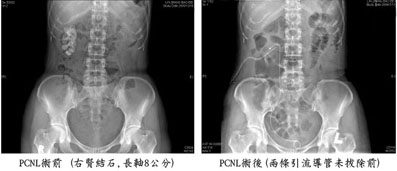

尿路結石的處理方法有許多種,包括現在普遍使用的體外震波碎石術(ESWL)、內視鏡手術及傳統開刀手術。對於巨大的腎結石或腎盂輸尿管交接處的結石,單用體外震波碎石術,往往無法一次完全擊碎,並且擊碎後常引起碎小結石阻塞輸尿管使病情愈趨複雜,這種情況最適合進行經皮腎造瘻截石手術(PCNL)

,將大部分的結石直接取出,若有殘餘結石,再配合體外震波碎石術,才可以獲得最好的效果。雖然與PCNL同時發展的體外震波碎石術在1984年後已大幅降低PCNL的臨床應用,PCNL在治療尿路結石上仍有其無可取代的地位,是治療尿路結石的重要方法。

PCNL於1976年由Fernstrom與Johannson完成首例,到1980年早期已是一趨近成熟的手術。傳統的手術方式是讓病患趴臥在手術檯上,胸腹部以枕頭墊高,使側腹得以向上突起,由X光透視結石的位置,在背部做腎臟穿刺。首先以穿刺針穿刺,經皮膚、腎臟皮質,通到腎盞內,先留置一條.035或.038的導線,再沿著導線以擴張管(Fascial dilator)將此腎臟通道擴張至24~30F,接著放置安氏套管(Amplatz sheath)當工作通道,方便腎臟鏡進出腎臟,將腎結石以水電波導線(electrohydraulic probe)、超音波碎石棒(ultrasonic lithotriptor)或震動碎石棒(lithoclast)擊碎,再以取石鉗(Forceps or basket)取出。手術結束前通常會在輸尿管及腎臟通道分別留置一條輸尿管導管及一條腎造瘻管,身體外表只有一個一公分左右的傷口。術後48小時拔除腎造瘻管即可準備出院,腎造瘻管拔除後遺留下的傷口會暫時滲尿,但24小時內通常會自行癒合。這種手術方式住院時間約在五天以內,比腎臟半切取石手術的方法輕鬆,而且對腎臟極少傷害。

這種平躺姿勢的手術方式於1990年首度由Valdivia報告,1998年報告累積557例、採用X光透視定位的手術成績,其手術效果良好,併發症的機率沒有增加,並且沒有一般醫師所擔心的腸穿孔併發症。以往採用趴臥姿勢,一大理由即根源於此,擔心平躺姿勢較有腸穿孔的危險;反而是曾有二篇醫學報告分別提出四百例及一千例趴臥姿態的手術成績,各有一例及二例大腸穿孔的併發症。我們自1998年12月即改採用平躺姿勢,結合超音波定位技術,至2003年12月累積完成315例手術,腎結石有294例(93.3%),大的阻塞性上端輸尿管結石有21例(6.7%)。其中178位男性(60.3%)、117位女性(39.7%),共295位病患,年齡從26到88歲,平均52.6歲。右側結石142例 (45.1%),左側結石173例 (54.9%);需進行第二次PCNL的有6位男性、14位女性,共20位病患(6.8%)。結石大小從 35到3603 mm2不等, 平均660 mm2。手術時間由65到290分鐘,平均156分鐘;結石廓清率0-100%不等,平均82%。有4例(1.3%)因腎臟通道消失不見而手術失敗。失血量 50到1000 ml,平均225 ml;有61例(19.4%)需輸血PRBC 2-4單位。45位高危險群病患,術後沒有因心肺血管併發症需住加護病房照顧;沒有重大併發症包括動靜脈瘻管或失血過多需要接受動脈栓塞或開刀手術止血;同時也沒有腸穿孔、氣胸或水胸等其它重大併發症。